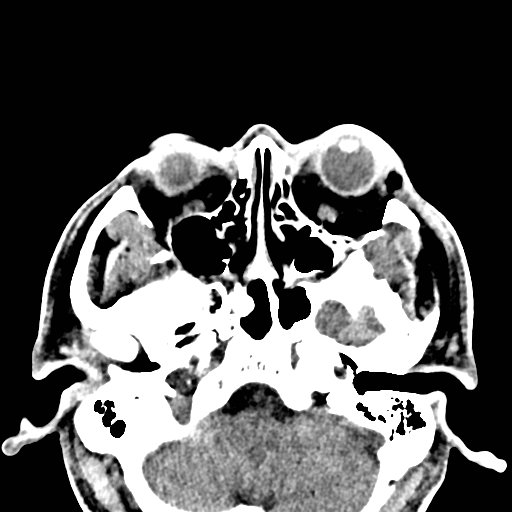

Physical exam showed marked left palpebral subcutaneous crepitus, as well as bulbar and palpebral conjunctival bulging. Visual acuity was normal with intact extraocular movements, and normal pupillary exam. Computed tomography (CT) imaging of the face was obtained and revealed multiple displaced fractures involving the left orbital floor and zygomatic arch associated with moderate periorbital and postseptal extraconal gas, resulting in orbital proptosis.